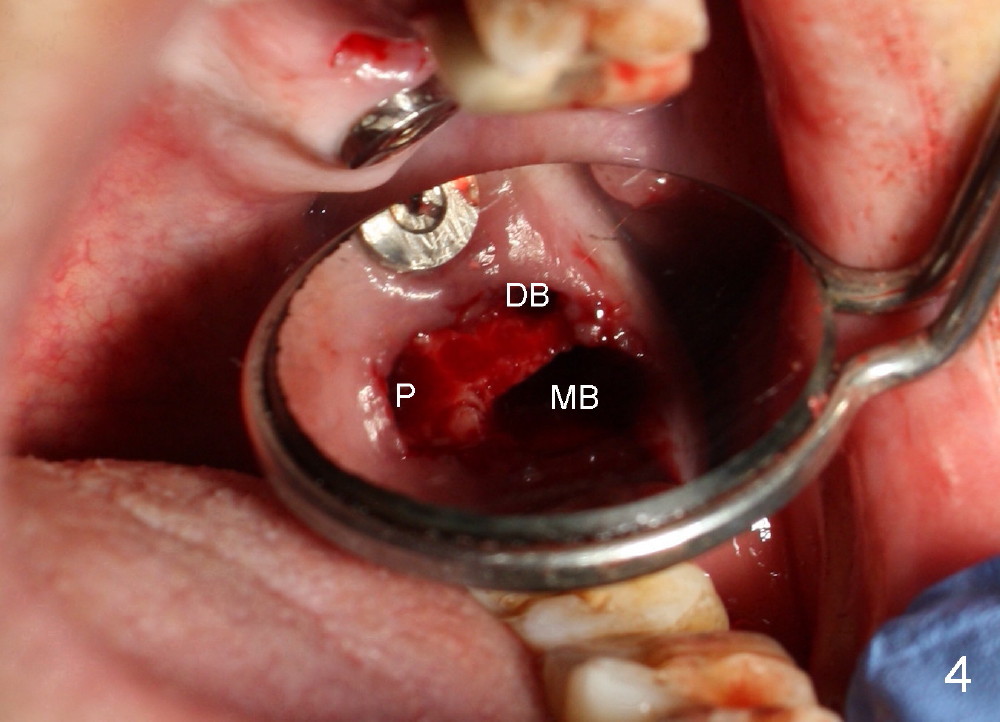

Fig.4 shows the septum between 3 roots (P: palatal, MB: mesiobuccal, DB: distobuccal) after extraction. Osteotomy is formed in the septum mainly by using osteotomes, followed by tap drill (Fig.5: 4.5x20 mm). When a 5x20 mm tap is removed, the osteotomy deviates buccally (Fig.6 arrowhead and MB). Finally a 5x20 mm implant is placed at the site of #14 (Fig.7).